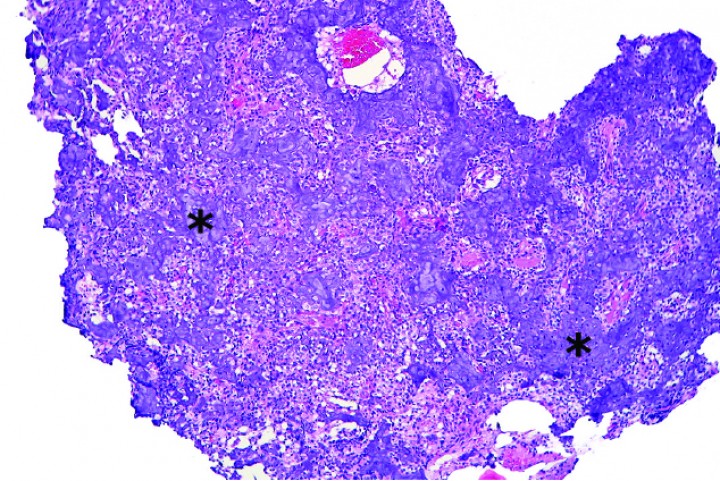

Histológicamente, estos condrosarcomas se caracterizaban por una proliferación de células poliédricas a fibrohistiocíticas o, más raramente, fusiformes dispuestas en nidos, haces o de forma sólida, con depósitos dispersos intercelulares de matriz basófila o anfofílica densa y, en algunos casos, matriz fibrilar eosinofílica que mostraba osificación endocondral o mineralización variable (Figs. 5, 6 y 7); ocasionalmente, se apreciaban zonas con estroma fibroso (Fig. 8).

<div class=\"Basic-Text-Frame\">

<p>Cobaya 2. Imagen microscópica de la biopsia de masa craneal. Se observa producción de abundante matriz cartilaginosa (asteriscos) por nidos de condrocitos neoplásicos dispersos entre dicha matriz. (Hematoxilina y eosina, x40).</p>

</div>

Figura 5

Cobaya 2. Imagen microscópica de la biopsia de masa craneal. Se observa producción de abundante matriz cartilaginosa (asteriscos) por nidos de condrocitos neoplásicos dispersos entre dicha matriz. (Hematoxilina y eosina, x40).